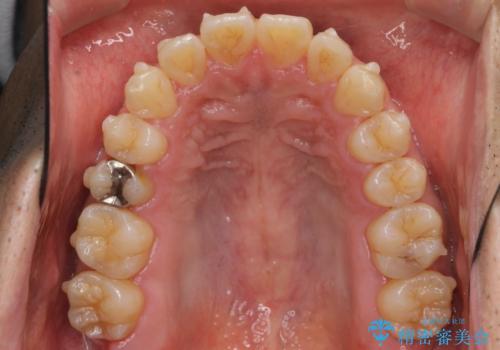

- 前歯のガタつきをきれいにしたい、と矯正治療を希望され来院されました。

マウスピース矯正インビザラインを用いてガタつきをきれいに並べていきます。

外側に傾斜していた前歯の角度も良くなり、「前歯の見た目が良くなった。」、と喜んでいただくことができました。